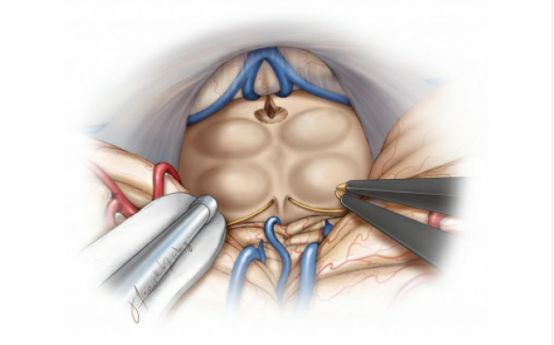

对于绝大部分松果体区肿瘤,笔者青睐于幕下小脑上(左侧)旁正中入路,这条入路通过沿着小脑幕面的下坡从侧方到达松果体区,提供了宽阔的手术通道,相对正中入路沿着小脑山顶进入,该入路能够触及位置更靠下方的肿瘤。

相对中线入路,该入路到达松果体区需离断的桥静脉更少,而且,从小脑幕面侧方的下坡进入可减少对小脑的强制性和固定牵拉。基于斜线的手术通道,使得对肿瘤对侧部分的显露充分许多,对于大型松果体区肿瘤的全切也更为轻松。但有时肿瘤与周围神经血管结构纤维性粘连,使切除程度受限。

图16. 图示为幕下小脑上(左侧)旁正中入路进入松果体区的手术通道。为了联合幕上入路,天幕可能被切开。但是这种间接的手术通道可能会使术者迷失方向。